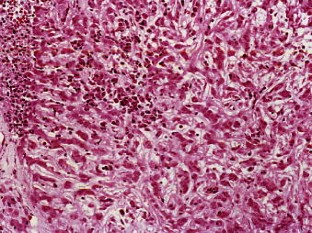

A chordoid glioma in the third ventricle was studied immunohistochemically and ultrastructurally. In this report, special attention is paid to the histogenesis in relation to the pathological appearance and unique anatomic location of this tumor. Light microscopic and immunohistochemical findings were similar to those reported previously. Ultrastructurally, microvilli were frequently seen, but three types of abnormal cilia were rarely observed. Basement membrane around the tumor cells and microvessels was extensive. Poorly to moderately developed intermediate (adherent) junctions were frequently seen. Resemblance of these ultrastructural features of the tumor to embryonic tanycytes suggests the tanycytic differentiation of chordoid glioma. Neuroradiologically, all of the previously reported cases of chordoid gliomas seem to arise in the anterior part of the third ventricular floor. This region includes the lamina terminalis, infundibular recess and median eminence, which corresponds to a tanycyte-rich area. These findings suggest a tanycytic origin of chordoid glioma.

Fig. 5.

Fig. 6.